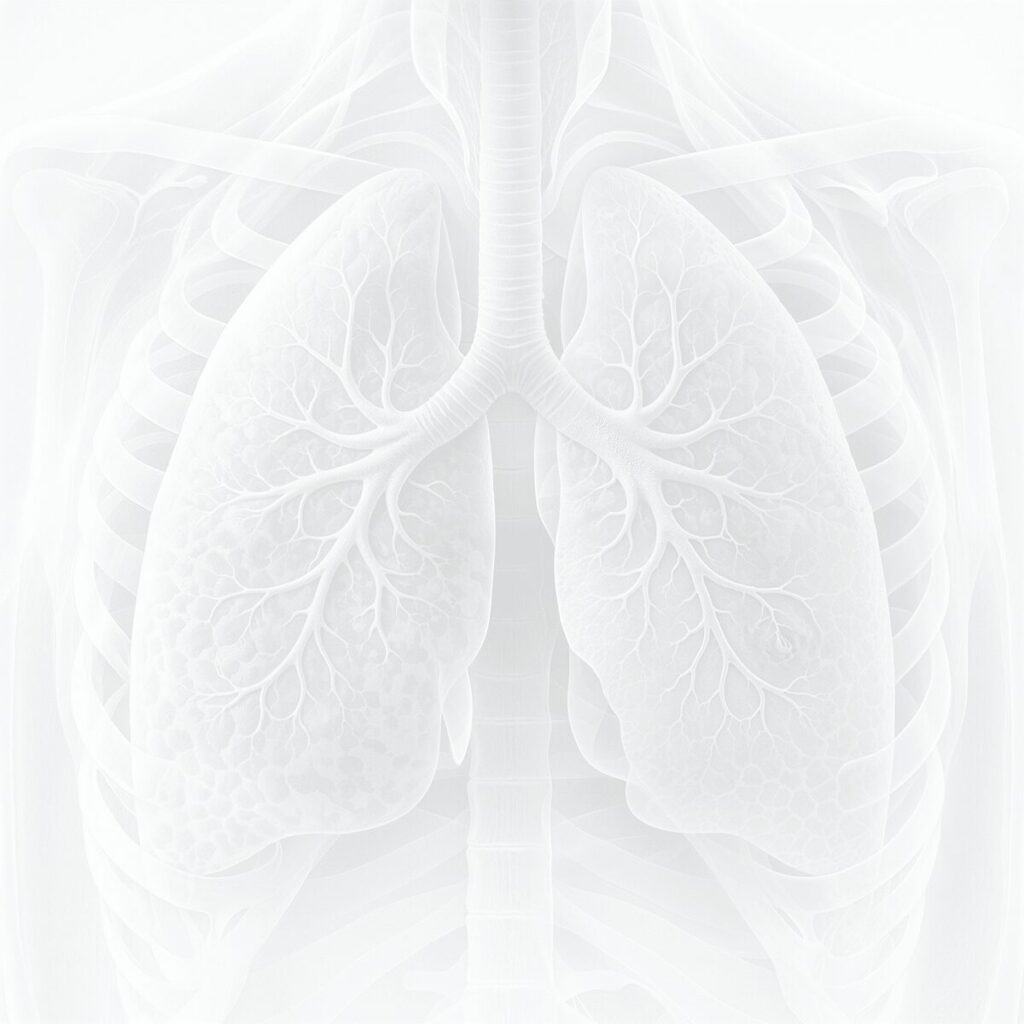

Lungenerkrankungen entwickeln sich häufig lange unbemerkt. Gerade deshalb spielt der Zeitpunkt der Diagnostik eine große Rolle. Wird zu spät untersucht, gehen wertvolle Chancen verloren. Wird zu früh oder ungezielt untersucht, drohen unnötige Unsicherheit und überflüssige Befunde. Gute Lungenfrüherkennung braucht deshalb den richtigen Moment – und die richtige Methode.

Menschen mit relevanter Raucheranamnese, früherem Nikotinkonsum oder weiteren Risikofaktoren haben ein erhöhtes Risiko für Lungenkrebs. Für genau diese Gruppen kann ein Low-Dose-CT sinnvoll sein, weil es kleine pulmonale Herde früher sichtbar machen kann als symptomorientierte Diagnostik.

Früherkennung ist nur dann nützlich, wenn sie risikoorientiert und medizinisch sinnvoll erfolgt. Zu langes Abwarten kann bedeuten, dass eine potenziell behandelbare Veränderung später entdeckt wird. Gleichzeitig sollte die Untersuchung gezielt bei den Menschen eingesetzt werden, die tatsächlich davon profitieren.

Auch in der Lungenfrüherkennung entstehen häufig Zufallsbefunde oder kleine Knoten, die nicht automatisch bedrohlich sind. Gute Radiologie unterscheidet, was harmlos, kontrollbedürftig oder abklärungswürdig ist – und verhindert dadurch unnötige Alarmreaktionen.

Besonders relevant ist Lungenfrüherkennung bei:

• Raucherinnen und Rauchern mit erhöhtem Risiko

• Ex-Raucherinnen und Ex-Rauchern

• familiärer oder beruflicher Belastung

• dem Wunsch nach strukturierter risikoorientierter Abklärung

In der Lungenfrüherkennung ist nicht nur die Technik entscheidend, sondern der richtige Zeitpunkt. Er bestimmt, ob Diagnostik wirklich einen Unterschied machen kann. Mehr zur Untersuchung und für wen sie sinnvoll ist, erfahren Sie auf unserer Seite zum Low-Dose-CT der Lunge.